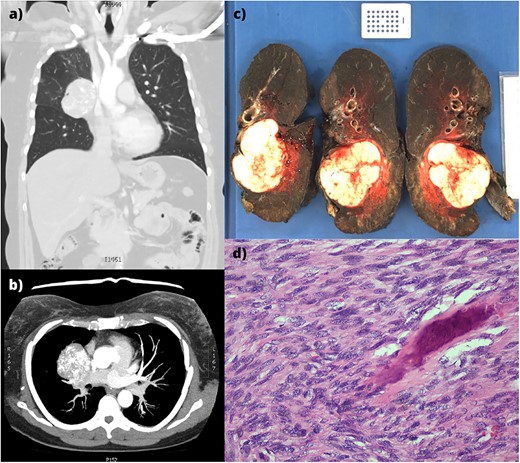

A 58-year-old female with a history of osteosarcoma arising from the right proximal humerus was initially treated with neoadjuvant chemotherapy, resection, and endoprosthetic reconstruction of the humerus, and a pedicled latissimus dorsi flap reconstruction. Four years later, a right middle lobectomy was performed for a metastasis, with histologically clear margins and no nodal involvement. Ten years following the lobectomy, she presented with a new cough. Computed tomography (CT) revealed a right hilar lobulated mass, measuring 7.1 cm × 5.6 cm × 5.9 cm, posteriorly displacing the right main bronchus (Fig. 1a and b). Positron-emission tomography showed significant uptake and an endobronchial ultrasound biopsy confirmed metastatic osteosarcoma.

(a,b) CT imaging showing a large right hilar mass with compression of right main bronchus and superior vena cava. (c) Macroscopic appearance of the right lung containing the tumour and adjacent mediastinal structures. (d) Histopathology of the metastatic osteosarcoma, demonstrating atypical spindle cell morphology.

An en bloc intrapericardial right completion pneumonectomy and mediastinal lymph node dissection was performed via median sternotomy. Two factors favoured this approach: the hostile hilum subjected to a previous lobectomy and avoiding injury to the pedicled latissimus dorsi flap used for the initial reconstruction. The lesion was abutting but not involving the superior vena cava. Following lung deflation, the pericardium was opened and the right pulmonary artery, pulmonary vein, and azygous vein were ligated. Station 7 lymph nodes were resected, and the right main bronchus was divided. The right lung, pericardium, phrenic nerve, station 4 and 10 lymph nodes were resected en bloc (Fig. 1c). The pericardium was reconstructed with expanded polytetrafluoroethylene (0.6 mm × 10 cm × 15 cm, W. L. Gore & Associates, Inc. Flagstaff, AZ, USA). The soft tissue and sternum were closed routinely.

Histologically, the solitary tumour was well-circumscribed and un-encapsulated with atypical spindle cells in intersecting fascicles (Fig. 1d). Hyperchromasia, pleomorphism, nuclear atypia, and high mitotic indices were demonstrated. Osteoid with calcification was present, confirming osteosarcoma. The bronchovascular margin and lymph nodes were not involved.